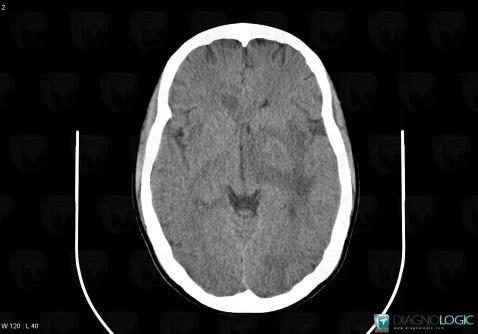

Toxoplasmosis, Cerebral hemispheres, CT

Here is the specific information in the key image above:

- Diagnosis Toxoplasmosis (link to Abscess), Location(s) Cerebral hemispheres, with gamuts Intracerebral lesion with ring enhancement, Intracerebral lesion with moderate enhancement, Multifocal intracranial lesions